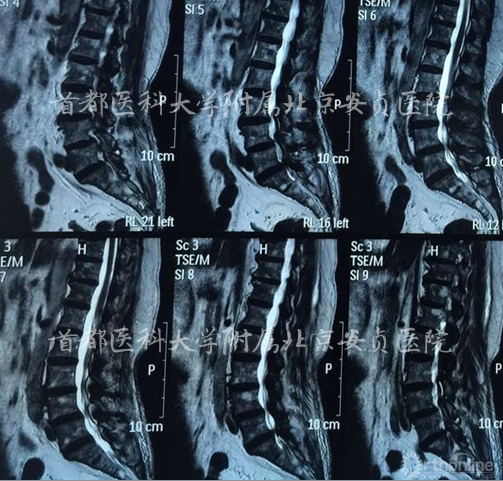

影像资料:

入院诊断:

脊髓型颈椎病、颈椎间盘突出症、腰4滑脱(l度)、腰椎管狭窄、高血压病、冠心病。

手术节段? C3/4+C5/6+C6/7

C5/6+C6/7

C5/6

C5/6 ACDF 术后2天

术后一个月

本例影像学检查结果示C3-4,C5-6及C6-7均有硬膜囊受压,但是结合症状、体征、高龄,我们选择C5-6为责任节段,进行了针对性的减压,取得了良好的效果。